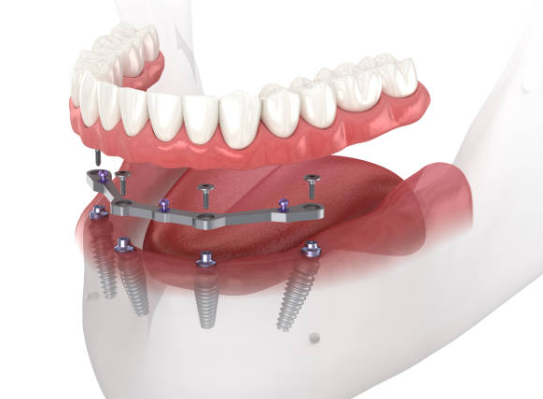

임플란트는 크게 세 부분으로 나뉘며, 치아 뿌리를 대신하는 구조물인 임플란트 (인공치근), 그 위에 체결을 하는 보철기둥 (지대주), 마지막으로 그 위에 씌우는 보철물 (크라운)이 있습니다.